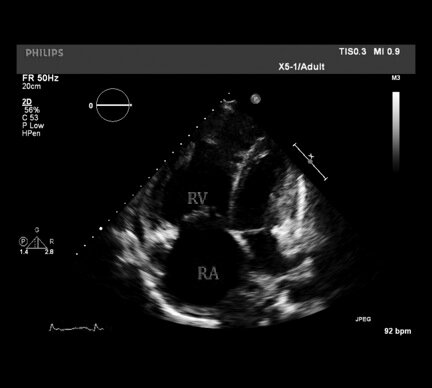

Most likely diagnosis:

1) pulmonary hypertension

2) restrictive cardiomyopathy

3) hypertrophic cardiomyopathy

4) pulmonary hypertension

Pulmonary Hypertension:

- RV > LV; RA > LA

-other findings can include:

right ventricular hypokinesis

septal flattening or bowing toward the left ventricle

tricuspid regurgitation

pulmonary insufficiency

midsystolic closure of the pulmonary valve